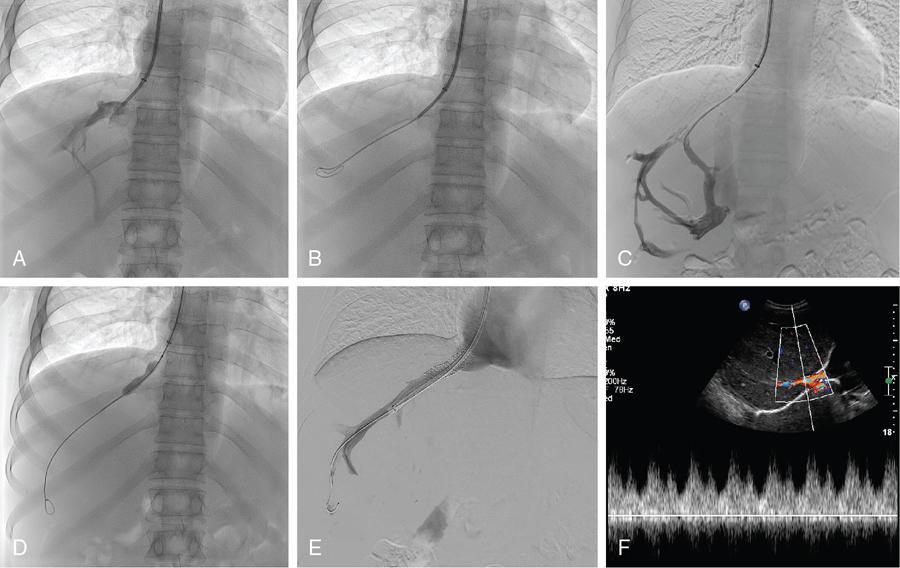

Chandan Jyoti Das, Abdul Razik Budd–Chiari syndrome (BCS) is the eponym for the clinical presentation occurring from hepatic venous outflow tract obstruction (HVOTO) anywhere between the small hepatic venules and cavoatrial junction. Obstruction at the sinusoidal level and those resulting from cardiac and pericardial diseases, do not come under BCS. Interventional radiology plays an important role in the management of BCS and has largely replaced surgical shunts. This chapter provides a brief review of some important clinical aspects of BCS, followed by detailed description of the interventional management. BCS can be primary, when obstruction occurs due to intraluminal pathology (e.g. thrombosis, webs) or secondary, when compression is caused by extrinsic pathologies such as tumours or abscesses. Based on the site of obstruction, three types exist (Table 9.27.1). The following discussion deals with only types I and II of primary BCS. There is a well-recognized demographic difference in the etiology and location of venous occlusion between the western and eastern populations. In the west, most cases occur secondary to prothrombotic conditions, with long segment or multifocal hepatic venous stenosis being the most prevalent patterns. The most common predisposing condition is usually a myeloproliferative syndrome, often with JAK2 V617F, JAK2 exon 12 or calreticulin mutations. Other prothrombotic conditions include inherited thrombophilia (factor V Leiden mutation, protein C, protein S and antithrombin deficiency), obesity, neoplasms (tumour-induced thrombophilia or direct tumour thrombus within the vein), autoimmune disorders (antiphospholipid syndrome, Behcet’s disease), paroxysmal nocturnal haemoglobinuria, pregnancy, oral contraceptive use and hyperhomocysteinemia. In 15%–20%, multiple predisposing factors may be present. In Asia, most cases possess short segment (<1 cm) fibrous web or membranous obstruction of the inferior vena cava (IVC), hepatic vein or both and demonstrate a more chronic course of the disease. Earlier considered congenital, the web has been recently attributed to organization of thrombus resulting from diarrhoea-related dehydration or postpartum sepsis. This is supported by the observation of higher prevalence of webs in patients of the low socioeconomic strata. More recently, the incidence of long-segment hepatic venous thrombosis has increased in the East, possibly from improved socioeconomic conditions. Most patients presenting with BCS in the developing countries are young adults. The presentation depends on the acuteness of the thrombus and may be fulminant, acute, subacute or chronic. Acute BCS presents with the classical triad of abdominal pain, hepatomegaly and ascites over a short duration (<1 month). In 5%, rapid progression of congestion to ischemic hepatocyte necrosis results in fulminant acute liver failure (jaundice, coagulopathy and encephalopathy). A gradually developing thrombus often permits the development of collateral vessels, which partially decompresses the congestion resulting in subacute (onset of symptoms over 1–6 months) or chronic BCS (onset over >6 months). Chronic BCS is overall the most common form and presents with manifestations of portal hypertension such as ascites and variceal bleeding. Some patients may be completely asymptomatic, with BCS being detected on evaluation for deranged liver function tests. Patients with IVC occlusion may have additional symptoms of prominent abdominal wall veins, lower limb edema and ulcers. At present, there are no randomized trials evaluating the different treatment protocols used in BCS. As such, most algorithms are based on retrospective studies or expert opinion. Asian patients with membranous/short-segment IVC or hepatic vein obstruction are excellent candidates for upfront angioplasty. On the other hand, in the West, where long-segment thrombosis is more prevalent, the American Association for Study of Liver Diseases (AASLD) advocates a ‘stepwise’ approach to escalation of invasiveness (Fig. 9.27.1). This involves initial medical management, and reserves the more invasive therapies (intervention/surgery) for nonresponders. Interventional therapies may be initiated early in patients with Rotterdam class III, high Clichy, high model for end-stage liver disease (MELD >18) and high Child–Turcotte–Pugh (CTP C) scores. Among these, the Rotterdam and Clichy scores, tailored specifically for BCS, predict early (3-month) mortality better than the CTP or MELD scores. Interventional therapies are classified as physiological (angioplasty, with or without stenting) or derivative (transjugular intrahepatic portosystemic shunt; TIPS). These therapies relieve outflow tract obstruction and the resultant stagnation, thereby improving liver perfusion. The specific treatment depends on acuteness of presentation, as well as the location and length of the involved venous segment. In acute fulminant liver failure and end-stage liver disease, once permanent damage has occurred, orthotopic liver transplantation (OLT) is indicated. After the advent of interventional procedures, surgical portosystemic shunts have been rarely used. Medical management involves anticoagulation; sodium-restricted diet and diuretics for ascites; beta-blockers for portal hypertension, as well as treatment of the predisposing factor. Anticoagulation is performed even in asymptomatic patients and those without predisposing factors as it improves long-term survival. It prevents thrombus propagation, rather than dissolution of an existing thrombus. Generally, anticoagulation is initiated with unfractionated or low-molecular-weight heparin (LMWH) till the effect of oral anticoagulants (vitamin K antagonists or direct thrombin inhibitors) takes over. Subsequently, oral anticoagulation is continued to maintain the target prothrombin time-international normalized ratio (PT-INR) in the range of 2–3. LMWH is preferred over unfractionated heparin in view of lower risk of heparin-induced thrombocytopenia. Thrombolysis restores hepatic outflow in patients with recent (acute or subacute) thrombosis who do not respond to early anticoagulation. It may be performed as systemic infusion through a peripheral vein or as direct infusion through a catheter placed in the hepatic artery or vein (catheter-directed or local thrombolysis). Best outcomes are seen in the acute phase, and in patients having a low thrombus load and some residual flow within the thrombus. Patients with higher clot load have poor outcomes since complete thrombolysis is difficult to achieve. Although no studies have compared systemic versus catheter-directed thrombolysis, the latter is preferred since it enables higher local concentration of the thrombolytic agent and better clot-to-drug contact, thereby increasing the chances of recanalization, while reducing the required dose and risk of remote bleeding. Catheter-directed thrombolysis involves the placement of a multisidehole catheter across the thrombus, followed by administration of the drug directly into the thrombus. After securing venous access through the jugular or femoral route, a catheter–guidewire combination is used to negotiate the length of the thrombus. Failure to advance the soft end of the guidewire through the thrombus (guidewire traversal test) indicates chronicity and predicts failure of lysis. Once negotiated, the infusion catheter is placed across the thrombus to bath the thrombus with the thrombolytic agent. An initial thrombus lacing is performed with a bolus dose of the drug using a ‘pulse-spray’ technique to enable pharmacomechanical disruption, followed by continuous slow infusion of the drug. Recombinant tissue plasminogen activator (rtPA, alteplase) is the most commonly used agent. The typical doses used are 5–10 mg initial bolus followed by 0.5–1 mg/hour. RtPA has a short half-life of 5 minutes, and earlier reversal is possible in case of bleeding complications. Streptokinase and urokinase are uncommonly used in view of their adverse safety profile and lower efficacy. In view of the risk of potentially fatal haemorrhagic complications, thrombolysis is contraindicated in patients with active bleeding and recent history of stroke, trauma, surgery or other invasive procedures (e.g. paracentesis within the past 24 hours). Concurrent heparin infusion (under activated partial thromboplastin time monitoring) is performed to prevent rethrombosis. During the infusion, the patient is monitored in a high-dependency unit and a repeat angiogram is obtained after 4–12 hours. The endpoints to thrombolysis are (a) complete lysis, (b) unchanged thrombus between two consecutive angiographic reviews and (c) occurrence of bleeding complications. Thrombus aspiration may be performed in conjunction with thrombolysis in acute thrombosis and when thrombolysis is contraindicated. In patients with subacute occlusive thrombus, portosystemic collaterals redirect hepatic circulation away from the hepatic veins, which results in suboptimal thrombus-drug contact and poor outcome following thrombolysis. In such cases, partial recanalization achieved using a balloon catheter improves the success of subsequent thrombolysis. In addition, partial hepatic decompression also reduces the risk of variceal bleeding during thrombolysis. In acute thrombosis, predilatation is better avoided in view of the high risk for pulmonary embolism, although a small balloon may be used cautiously. In many cases, thrombolysis wuncovers an underlying segmental venous stenosis or membrane which initially predisposed the thrombus. In such cases, postthrombolysis angioplasty would be required to achieve optimal luminal patency. Balloon angioplasty is performed in short-segment stenosis or membranous occlusion of the vein. Restoring flow in one of the three hepatic veins is sufficient to decompress the liver and relieve the symptoms. The best candidate vein is the one with a healthy proximal segment and is identified by its straight course, good calibre (7–8 mm) and echo-free lumen. Hence USG assessment is crucial for planning angioplasty. IVC is accessed through the transjugular approach using a 9/10-F, 40-cm long introducer sheath and half the bolus dose of intravenous heparin is administered. A cavogram is obtained to assess IVC patency and look for a residual hepatic venous stump. Any IVC stenosis resulting in impaired flow, collateral formation and significant pressure gradient requires angioplasty. However, in many cases, IVC may be compressed by a caudate lobe enlargement with normal flow across, in which case angioplasty is not required. A 5-F multipurpose angiographic catheter is used to cannulate the hepatic vein stump and wedge the stenosis. Subsequently, the stenosis is negotiated using the floppy end of a straight tip hydrophilic guidewire placed coaxially within a catheter, and exchanged for an Amplatz extra stiff guidewire. Once crossed, the completion dose of heparin is provided and angioplasty is performed using an 8–10 mm balloon catheter (5%–10% oversized compared to the lumen). In case there is difficulty in negotiating a tight fibrotic stenosis, the hard back end of the guidewire or a metallic needle (Colapinto needle or Rösch–Uchida trocar stylet) may be used. Ample caution must be taken to prevent inadvertent nontarget puncture and complications such as hemopericardium, haemothorax and pericaval haematoma. The procedure is demonstrated in Figs 9.27.2 and 9.27.3.

Angioplasty and stenting

Hepatic angioplasty